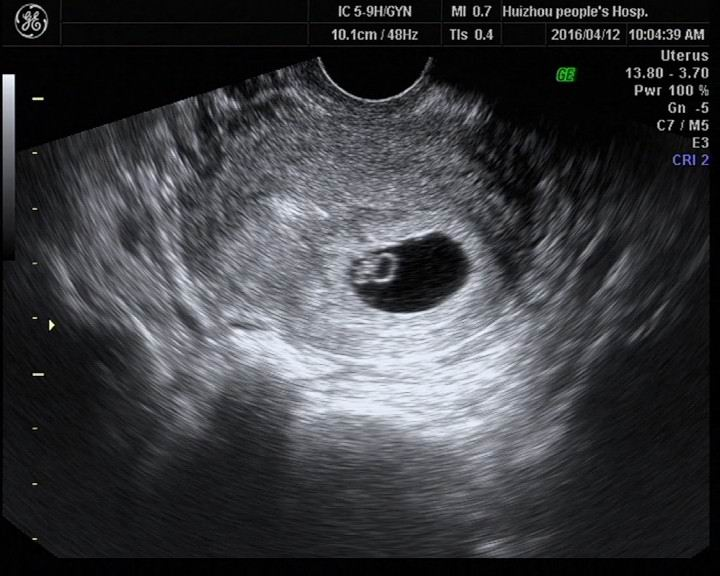

早孕,B超能照出“啥”?

很多人一驗到懷孕就會來醫(yī)院,但是很多媽媽不是很了解孕早期B超主要檢查什么。其實在早期B超主要檢查的內(nèi)容包括有:

①孕囊位置,以鑒別宮內(nèi)早孕和宮外孕,這是很多人都想知道的,因為一旦宮外孕大出血的話,很容易失去生命;

②孕囊大小,判斷孕囊與孕周是否相符;

③有無卵黃囊、胚芽和胎心,評價胚胎發(fā)育情況;

④判斷孕囊旁有無積液;

⑤子宮和卵巢狀況,及時發(fā)現(xiàn)子宮肌瘤和卵巢囊腫等異常。

一般說,在經(jīng)陰道超聲檢查下,孕5周左右可檢測到孕囊和卵黃囊,經(jīng)腹超聲最早6周可查見,它的出現(xiàn)是確定宮內(nèi)妊娠的標志,胚芽在孕40~50 天形成,胎心在孕50~60 天出現(xiàn),出現(xiàn)心管搏動可確定為活胎。若平時月經(jīng)延遲,則可能排卵滯后,那么卵黃囊、胚芽和胎心出現(xiàn)的時間也會相應延后。